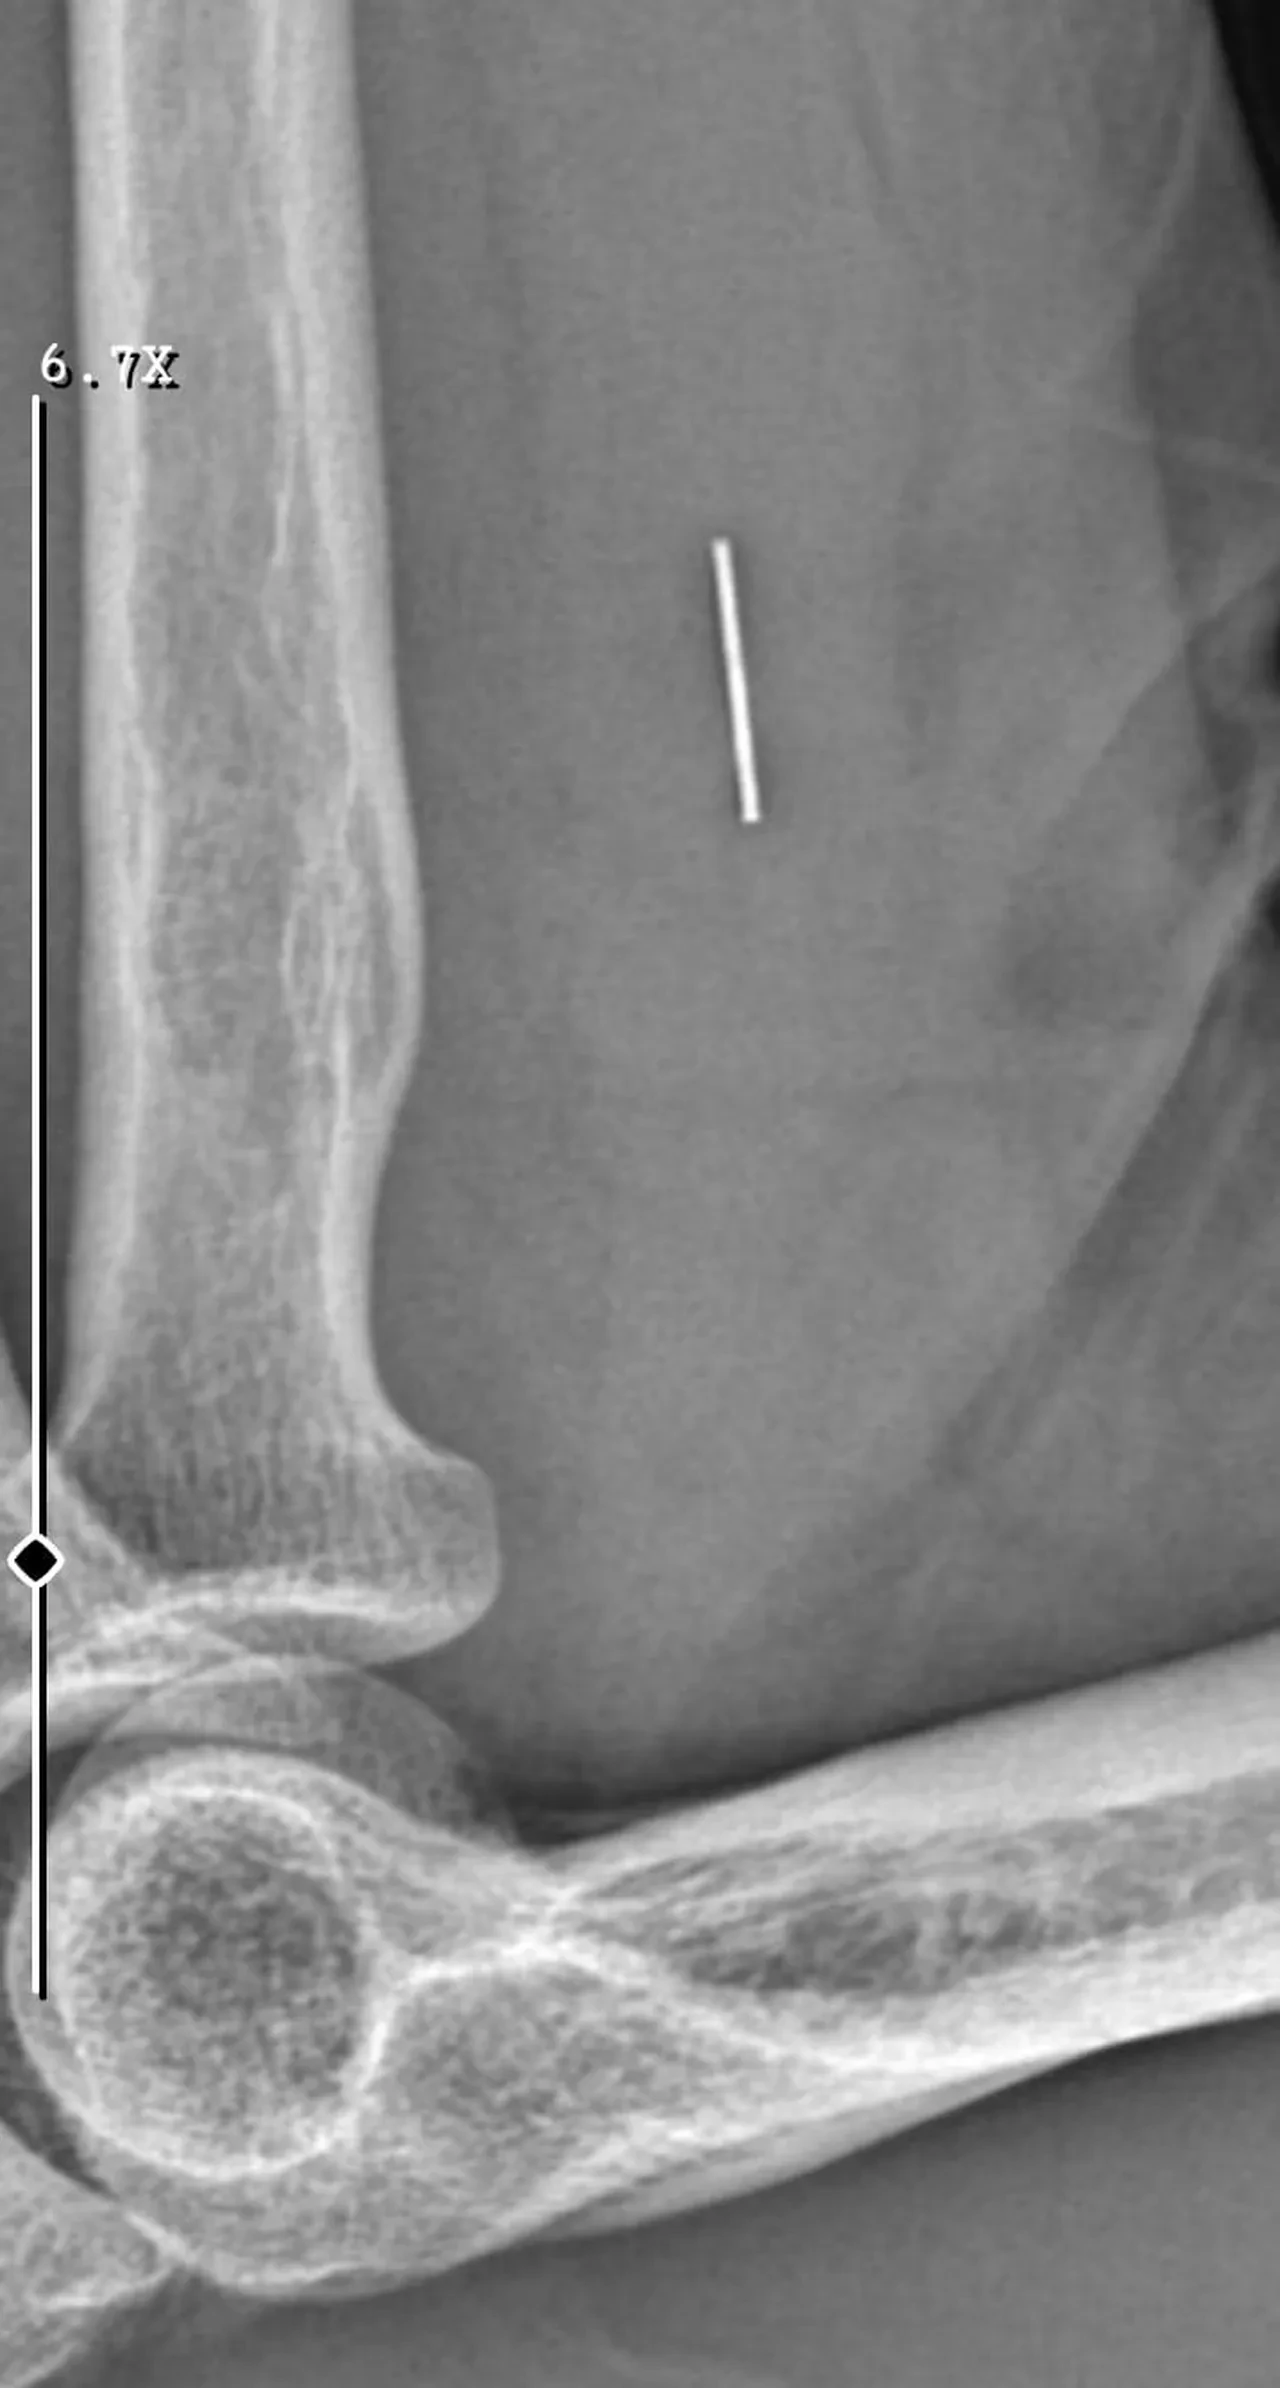

Diğer yandan, ameliyatların ardından ağrıları devam eden Güleryüz'ün kolunda metal parça bulunduğu ve bu parçanın parmak bölgesinden dirseğe doğru ilerlediği öne sürüldü. Ayrıca, fabrikada temizlik personeli olarak çalışan Nurettin Güleryüz'ün hastane sürecinde işten çıkarıldığı da öğrenildi.

"Doktorlara bileğime doğru ağrılarım olduğunu sürekli ifade etmeme rağmen beni dinlemediler. Sonradan kolumda metal kaldığını öğrendik. Bunun ihmal olduğunu düşünüyoruz. Çünkü kola metal nasıl girebilir? Ben 9 aydır çalışamıyorum. Kalp rahatsızlığım sebebiyle yüzde 46 engelliyken şu anda yüzde 75 engelli durumuna düştüm. Erken emeklilik dilekçesi verdim ancak henüz sonuç gelmedi. Bu konuda çok mağdurum. Yetkililerin bunu duymasını istiyorum. Savcılığa suç duyurusunda bulunduk. Yaklaşık 9 aydır henüz soruşturma izni gelmedi. Süreci bekliyoruz, henüz dava açılmış değil. Kolumda bırakılan metal ilerliyor. Pazartesi günü bunun için de operasyon geçireceğim. Çıkarılıp çıkarılamayacağı net değil. Elimde titremelerim var, çalışamıyorum ve işveren tarafından işten çıkarıldım. Yetkililerden destek ve konunun incelenmesini talep ediyorum."